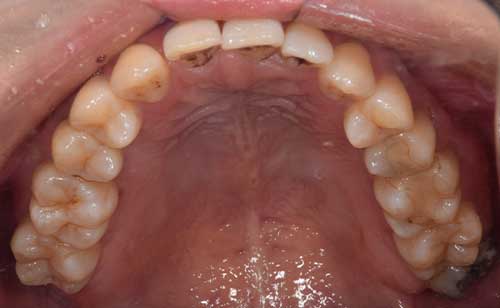

上顎はしっかり親知らずがはえています。下顎は右側は(青色)しっかりはえていますが、虫歯になっています。下顎の左側(赤色)は斜めにはえています。またこちらも虫歯になっています。

この場合、右側上下は残して、左側上下は抜くことがファーストチョイスになります。しかし、左上の6番目の歯(緑色)は根の治療をしており、虫歯にもなっていそうですので、左上の親知らずは移植歯として残しておいても良いという判断になります。

もちろん、患者様が移植は考えてなく、抜歯をしたいということであれば、抜歯を行います。